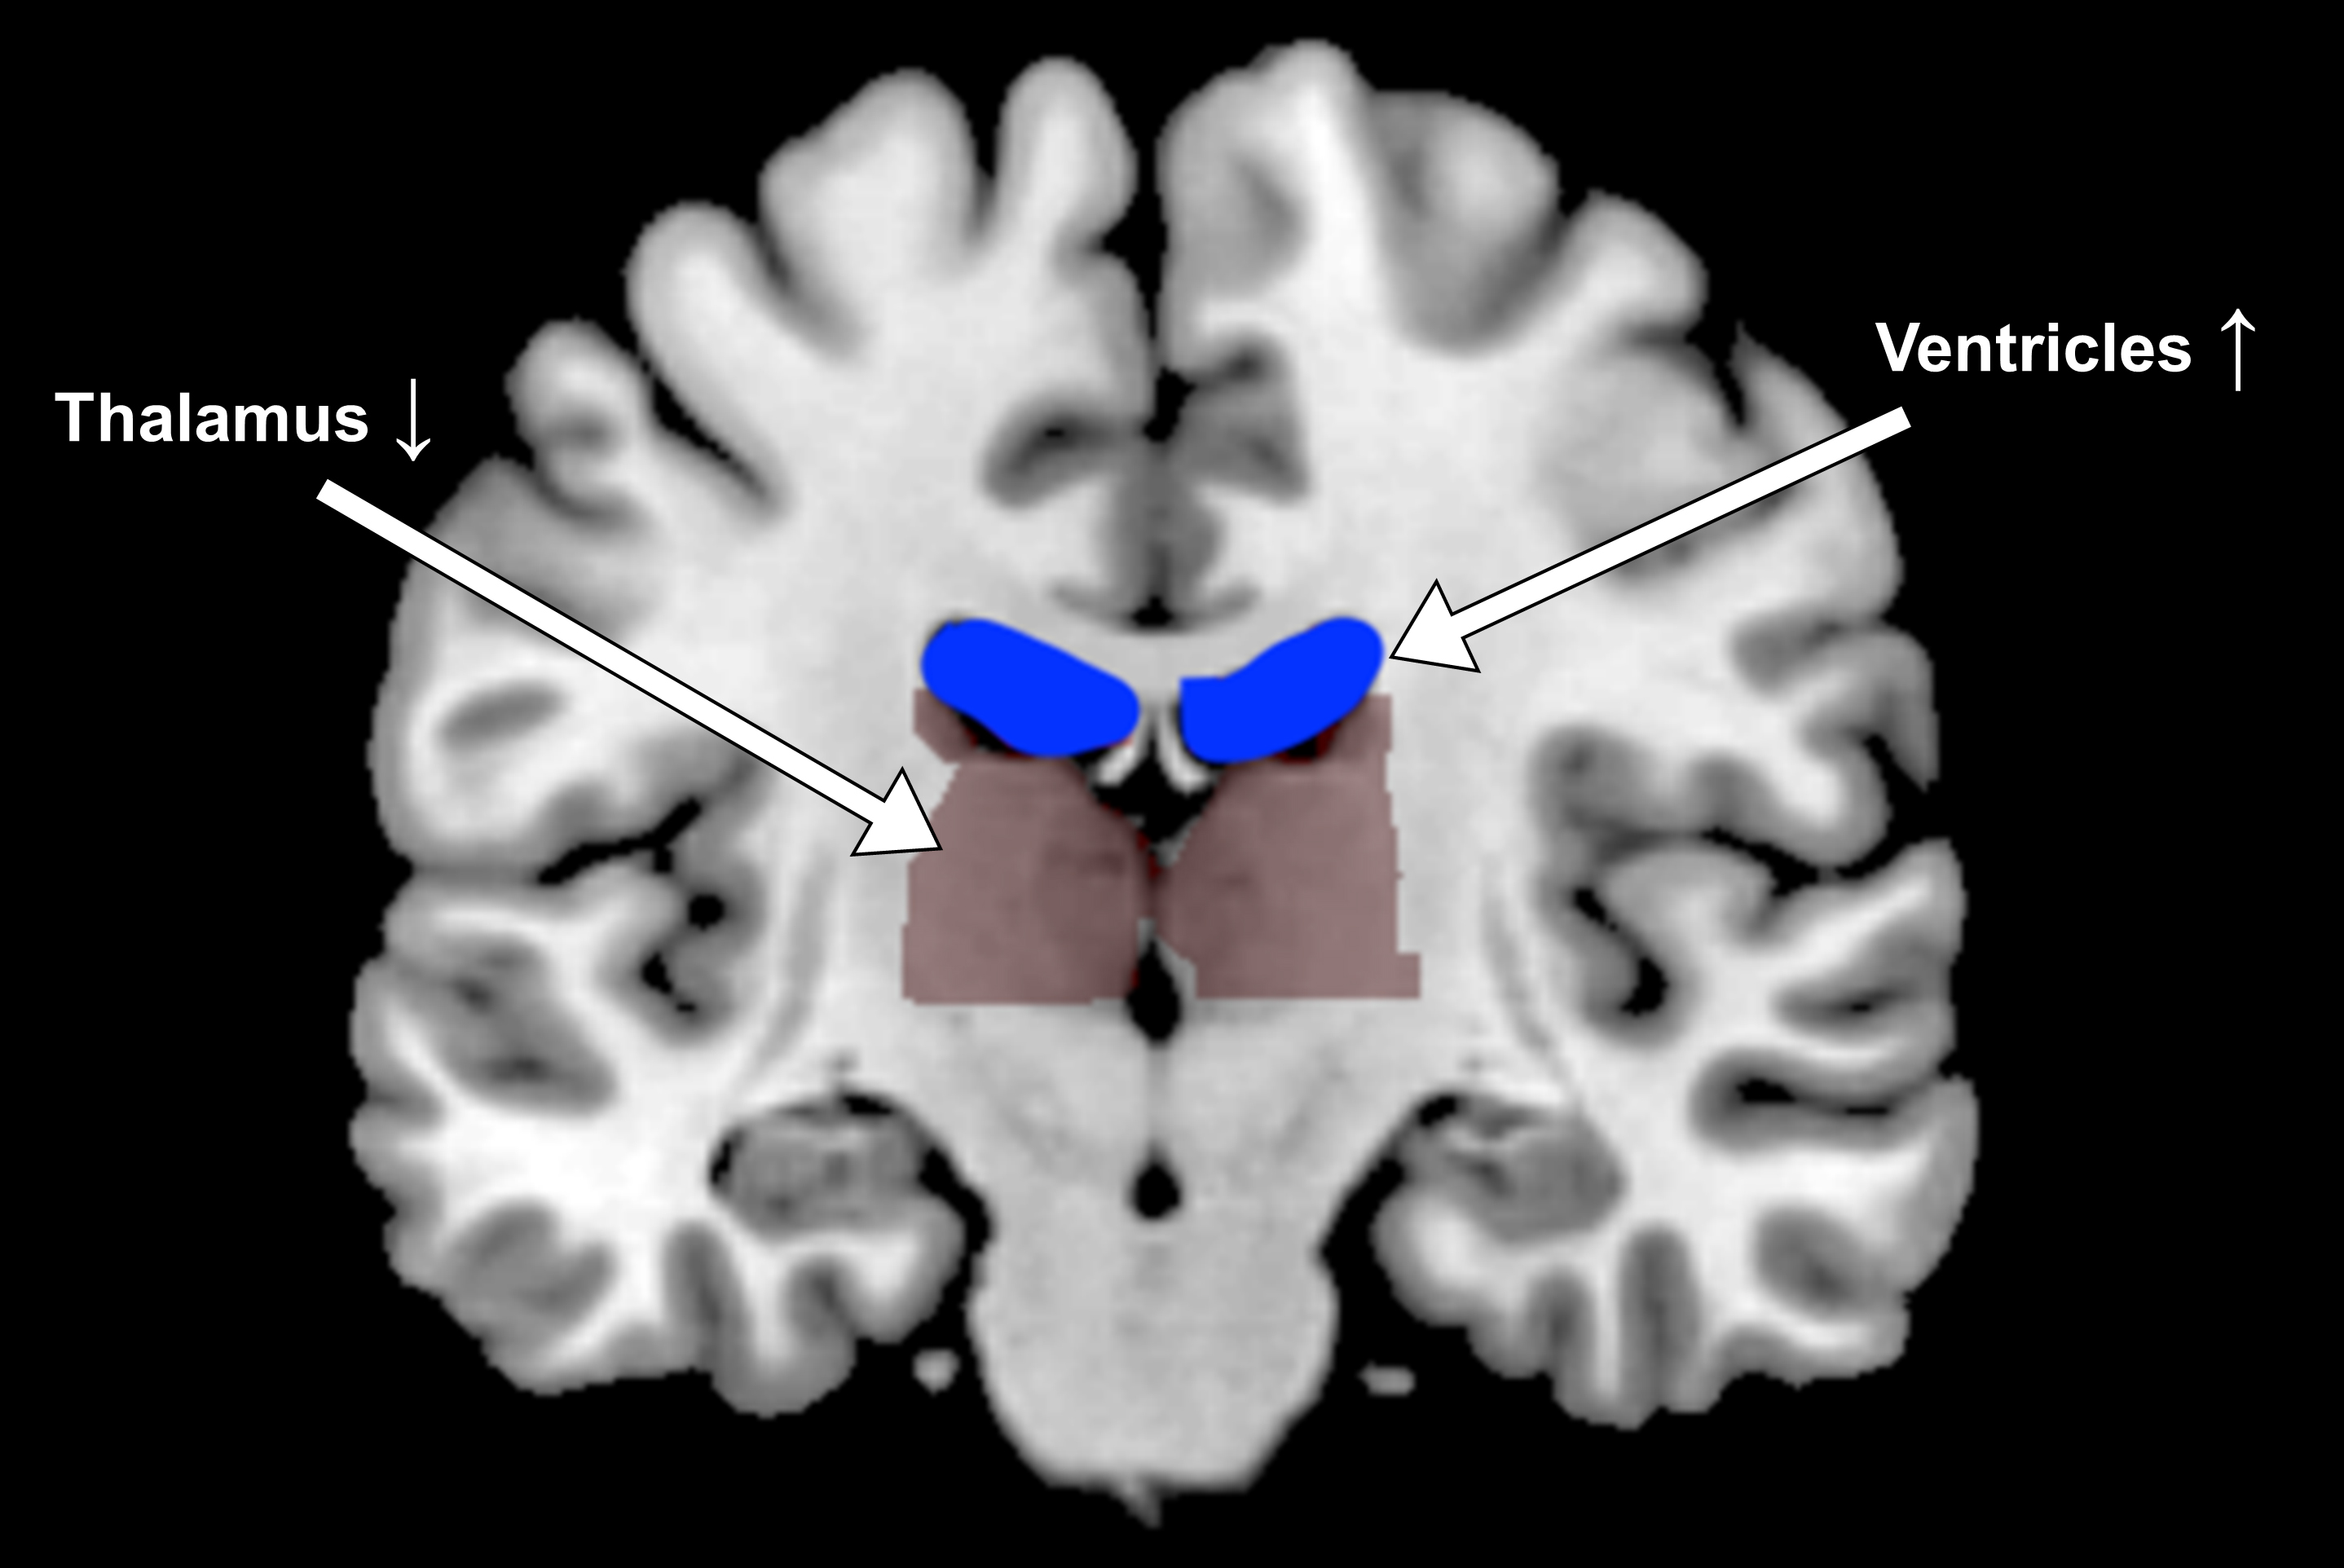

In the experiments, when participants exercised, sweated and drank water, fluid-filled spaces called ventricles in the center of their brains contracted. But with exertion plus dehydration, the ventricles did the opposite; they expanded.

Functional magnetic resonance imaging (fMRI) revealed the differences. Oddly, the ventricle expansion in dehydrated test subjects may not have had much to do with their deeper slumps in task performance.

“The structural changes were remarkably consistent across individuals,” said Millard-Stafford a past president of The American College of Sports Medicine. “But performance differences in the tasks could not be explained by changes in the size of those brain areas.”